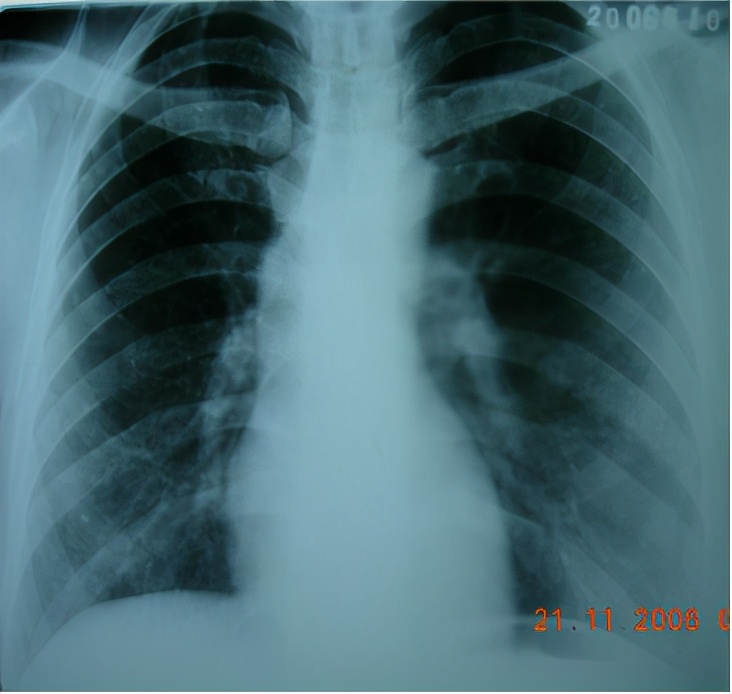

1)CXR

急性和亚急性过敏性肺炎的影像学有时很难区别,CXR有以下几种表现:可能是磨玻璃样或双肺纹理模糊,以下肺野明显;有时候会出现4-6周消失。

急性和亚急性过敏性肺炎的胸部CT的差距就比较明显,我们可以看到典型改变:小叶中心结节,边界不清,弥漫分布;轻症患者CT也可无明显异常;磨玻璃样/实变,片状或弥散,支气管血管束,下叶分布;肺气肿或马赛克征象。

因此,胸部CT可以发现CXR没有显示的病变,典型异常改变提示HP。